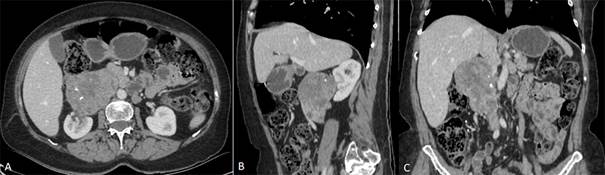

La tomografía computada (TC) evidencia una masa retroperitoneal de 86mm x 70mm x 102 mm, la cual envuelve la vena cava inferior (VCI), invade la grasa perirrenal y contacta con la pelvis renal (figura 1), se complementa con Angiotomografìa que confirma infiltración de la vena cava inferior.

Figura 1: TC de abdomen en fase portal. A) Imagen axial donde se observa masa retroperitoneal bien delimitada, con realce heterogéneo con el medio de contraste, presenta calcificaciones centrales. Engloba completamente la VCI. B) imagen en sagital donde se observa contacto con el riñón derecho, en C) imagen coronal donde se observa la extensión longitudinal del tumor y el compromiso de la VCI.